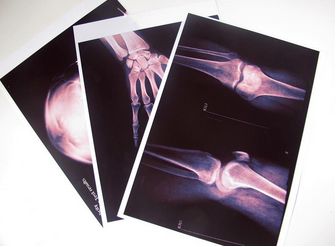

醫(yī)用X光膠片主要分為綠敏片和藍敏片兩種,其特點就是要與增感屏聯(lián)合使用,借助于X線在增感屏上的熒光作用使膠片感光。醫(yī)用膠片區(qū)別很多,種類分為標準型、高感光度型、

醫(yī)用X光膠片主要分為綠敏片和藍敏片兩種,其特點就是要與增感屏聯(lián)合使用,借助于X線在增感屏上的熒光作用使膠片感光。醫(yī)用膠片區(qū)別很多,種類分為標準型、高感光度型、超 高感光度型、寬容度型和微粒型。

感藍片的光譜特征是,峰值為420nm,對應著藍紫色光,配藍色熒光增感屏使用;感綠片的光譜特征是峰值550nm,對應黃綠色光,配和綠色熒光增感屏使用。對X光射線敏感的膠片其特點是,不要增感屏,利用X線直接照射感光,主要用于軟組織攝影。但是這種X光膠片的優(yōu)點是影像層次豐富,銳利度較高,但是缺點也是顯而易見的,組織對比度偏低。

間接攝影用X線膠片,此類膠片為單面乳劑涂布。對熒光屏發(fā)出的黃綠色光或監(jiān)視器光譜敏感性較高。特點就是要在自動傳送裝置中使用,強調傳遞的準確性。比如在熒光縮影處、CT片、MR片、X線電影片等。T顆粒X線膠片其結構特點是銀鹽顆粒所傳流顆粒要小,外形呈偏圓形,表面積比傳流顆粒要小,吸收射線多,感光迅速。優(yōu)點就是影像清晰,層次豐富,同時減少曝光了。

激光膠片是伴隨激光打印機發(fā)展起來的一種新型感光材料,是一種單面乳劑層膠片,由保護層、乳劑層、底層、片基層及防光暈層組成。

干式激光片不含鹵化銀,其表面是均勻涂抹的碳粉,對日光不敏感,可在明室操作,也不需化學處理。膠片的片基分透明片基和藍色片基兩種,片基上的碳粉只對激光起反應。根據(jù)圖像大小,相機自動選擇適當?shù)南袼卮笮 <す馐賹⒚總€像素分成的點打印,形成層次分明、邊緣銳利、不同灰階的圖像。膠片在干式打印機內成像后,原有的兩層保護膜脫掉,在碳粉層圖像兩面再各壓一層保護膜。